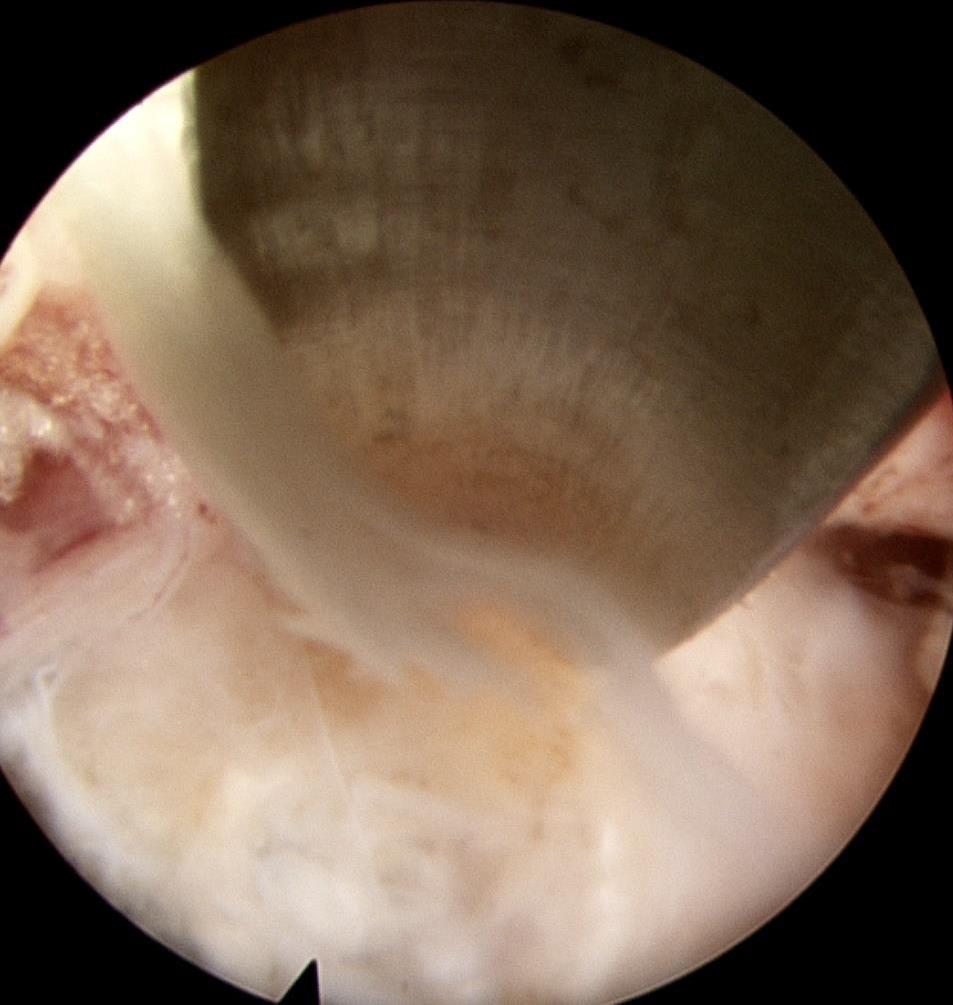

• 可旋转重复开闭软组织夹联合外科尼龙缝合线法闭合结直肠内镜黏膜下剥离术后缺损的临床应用价值

2025, 31(12):77-82. DOI: 10.12235/E20250091

摘要 (77) HTML (65) PDF 1.86 M (64) 评论 (0) 收藏

摘要:目的 探讨可旋转重复开闭软组织夹联合外科尼龙缝合线法(ROLM)闭合结直肠内镜黏膜下剥离术(ESD)后黏膜缺损的临床疗效。方法 回顾性分析2024年1月-2024年6月15例在南京医科大学附属常州市第二人民医院因早期结直肠肿瘤行ESD,并采用ROLM闭合黏膜缺损患者的临床资料。观察患者病灶相关情况(病灶部位、缺损最大径和术后病理)、手术相关情况(术后缺损成功闭合率、钛夹使用数量、ROLM缝合时间和住院时间)、术后并发症发生情况和术后随访情况。结果 术后缺损成功闭合率为100%。病灶长径3.0~6.0 cm,平均(3.7±0.8)cm。缺损部位:回盲部1例,升结肠6例,横结肠肝曲1例,降结肠2例,乙状结肠3例,直肠2例。术后病理为:管状腺瘤8例,黏膜下囊肿1例,管状绒毛状腺瘤5例,胃肠道间质瘤1例。钛夹使用数量为7~20枚,中位数为11(10,13)枚。ROLM缝合时间为13~37 min,平均(19.3±6.5)min。住院时间4~9 d,平均(6.5±1.2)d。术后无出血、穿孔、感染和消化道狭窄等并发症发生。术后3~6个月复查肠镜,手术创面均愈合良好。结论 ROLM能够安全、有效地闭合结直肠ESD后黏膜缺损。值得临床推广应用。